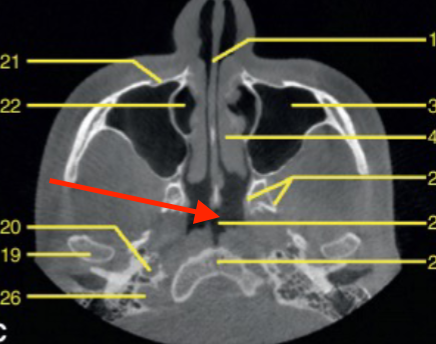

axial

what plane is this

lateral pterygoid plate

what structure is the arrow pointing to